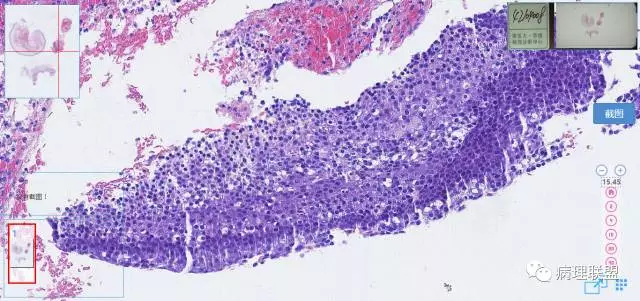

第一例

第一例和第二例病例我把典型图像压下来,是让我们以后注意,典型里找不典型,毛母质瘤主要由两种细胞构成,嗜碱细胞和影细胞构成,主要认识嗜碱细胞。